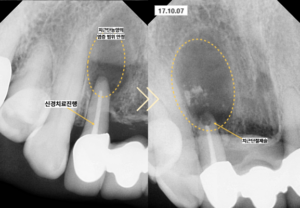

검사 결과 앞니 치아 뿌리 부위에 발생한

치근단농양의 크기가 치아 크기보다

더 크게 관찰될 정도로 매우 심한 상태였습니다.

먼저 신경치료를 통해 치아 내부의

감염원을 제거하고 치근단농양의 크기를

최대한 줄이는 과정을 진행하였습니다.

신경치료 후 염증의 범위가 안정된 것을 확인한 뒤

치근단절제술을 통해 잔존해 있던

염증 조직을 완전히 제거하였습니다.

치료 결과

전치부의 치근단농양은 완벽하게 제거되었고

손실되었던 치조골 역시 시간이 지나면서

100%에 가까운 재생이 관찰되었습니다.

집중치료기간은 약 2달로 이후 1년뒤에도

보존이 잘 이루어지고 있음을 확인할 수 있습니다.